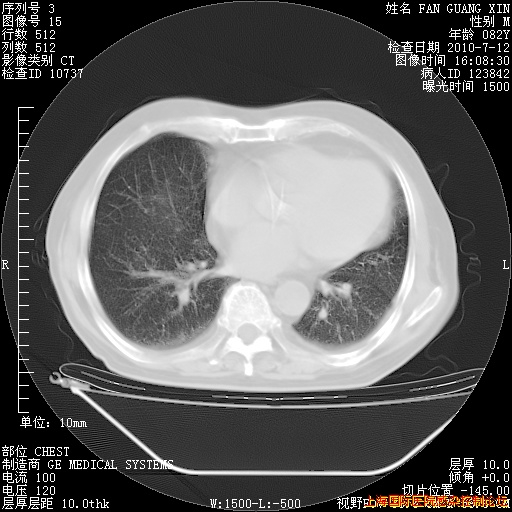

今天复查CT

今天CT

整整相隔30天的肺部CT好像有所好转啊。甲强龙减量第3天,需要观察体温。